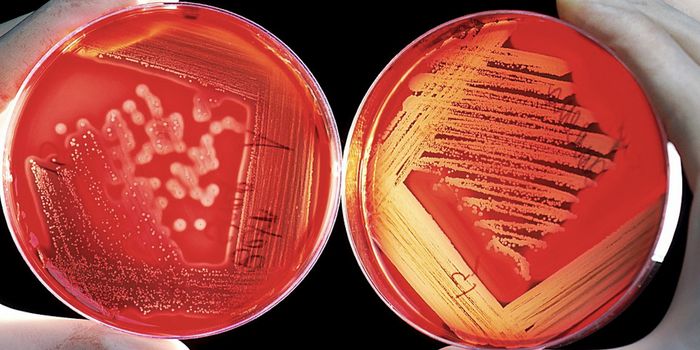

MAR 30, 2022Clinical & Molecular DXStrategies to Improve Your Lab’s Blood Culture Process A blood culture is a routine laboratory test in which blood ...

JUL 21, 2021MicrobiologyBlood culture is the most widely used diagnostic tool for the detection of bacteremia and fungemia. It is the most impor ...

APR 05, 2021MicrobiologyMany types of bacteria often live harmlessly in and on animals and humans, but some bacteria pose a threat. Salmonella b ...